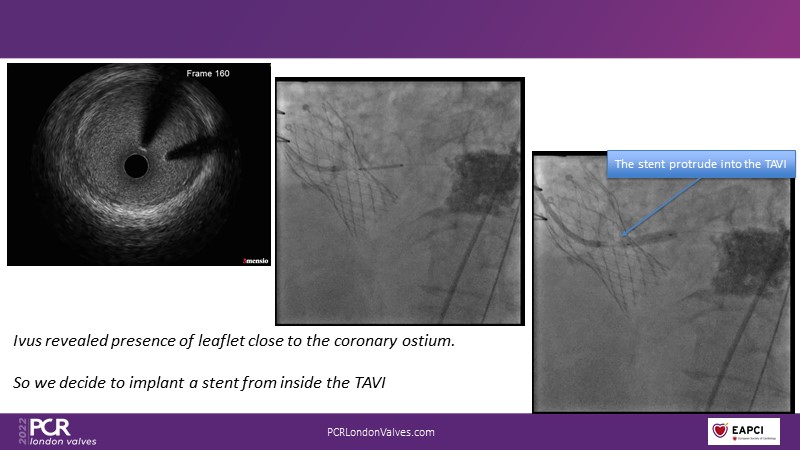

This session reflects on the importance of device choice and implantation technique in complex TAVI procedures. Learn how to anticipate the risks of a valve-in-valve procedure in small surgical prostheses, and discover the latest technological evolutions for treating patients with complex anatomy.

- To appreciate the importance of device choice and implantation technique in complex TAVI procedures

- To learn how to anticipate the risks of a valve-in-valve procedure in small surgical prostheses